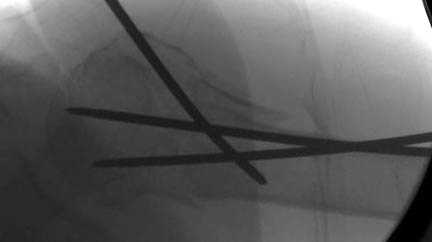

Наличие рентген контроля (ЭОП) помогает во время

репозиции и фиксации, но многие коллеги умудряются без рентгена фиксировать несколькими спицами перкутанно.

Наш недавний случай перкутанной фиксации "методом

Сиэтла" спицами 2.8 мм с резьбой на конце.